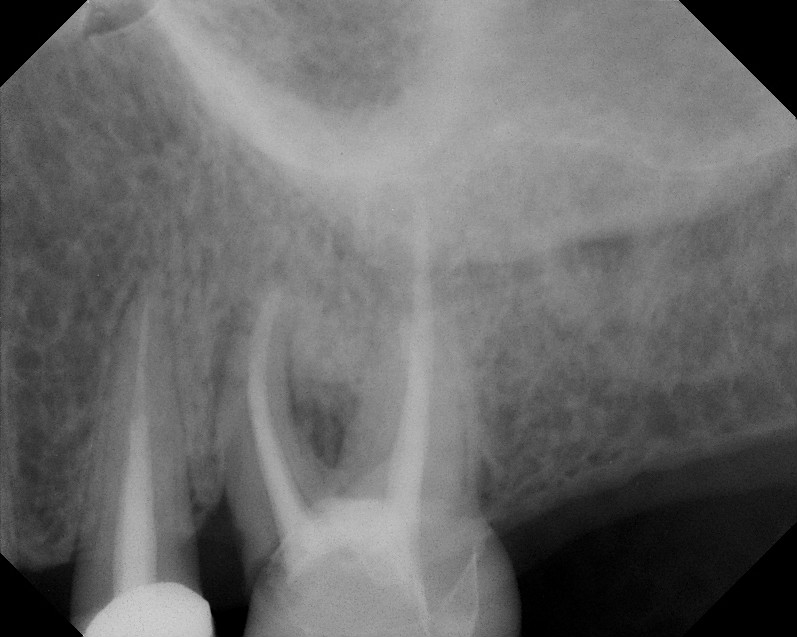

From www.theendoblog.com

The Endo Blog Diagnosing Root Fractures Vertical Root Fracture X Ray in this review, the diagnosis of vertical root fractures is discussed in detail, and examples are presented of clinical. vertical root fractures (vrfs) present extremely challenging diagnostic tasks in dental practice. a vertical root fracture (vrf) is a root fracture extending along the longitudinal axis of roots and is often. The diagnosis of vertical root fracture can. Vertical Root Fracture X Ray.

The Endo Blog Is That a Root Fracture? Vertical Root Fracture X Ray vertical root fracture (vrf) is one of the most common reasons for tooth extraction, although various methods have. The author conducted a study to relate subjective,. vertical root fracture (vrf) requires root removal. vertical root fracture (vrf) is a common reason for the extraction of root filled teeth. the incidence of vertical root fracture (vrf) is. Vertical Root Fracture X Ray.